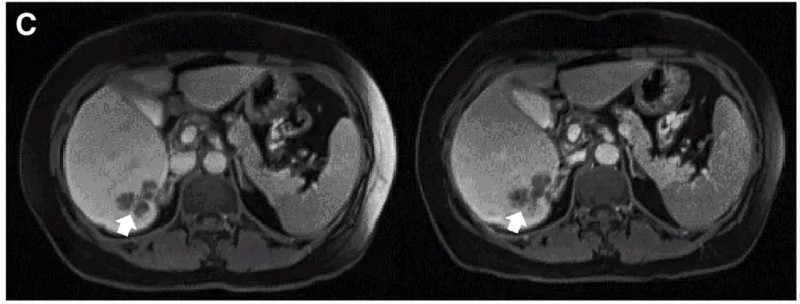

其中一个典型病例(P10患者)的治疗效果尤为亮眼:该患者在接受DL4剂量CEA CAR-T细胞治疗后,MRI证实肝内一处病灶缩小,下图显示了该患者在CAR-T治疗前(左图)、治疗4周后(右图)的MRI对比。

▲图源“Molecular Therapy”,版权归原作者所有,如无意中侵犯了知识产权,请联系我们删除